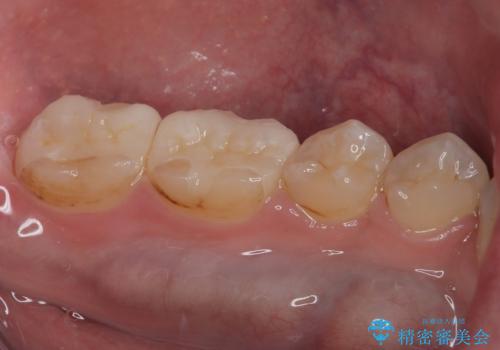

銀歯を白くしたい セラミックインレー修復

歯と歯茎の間に圧排糸と言われる糸を入れてシリコーン印象材にて精密な型どりをしました。

セラミックインレーの装着時には、唾液の侵入を防ぐために、ラバーダム防湿を行いました。

金属がなくなり大変満足していただけました。